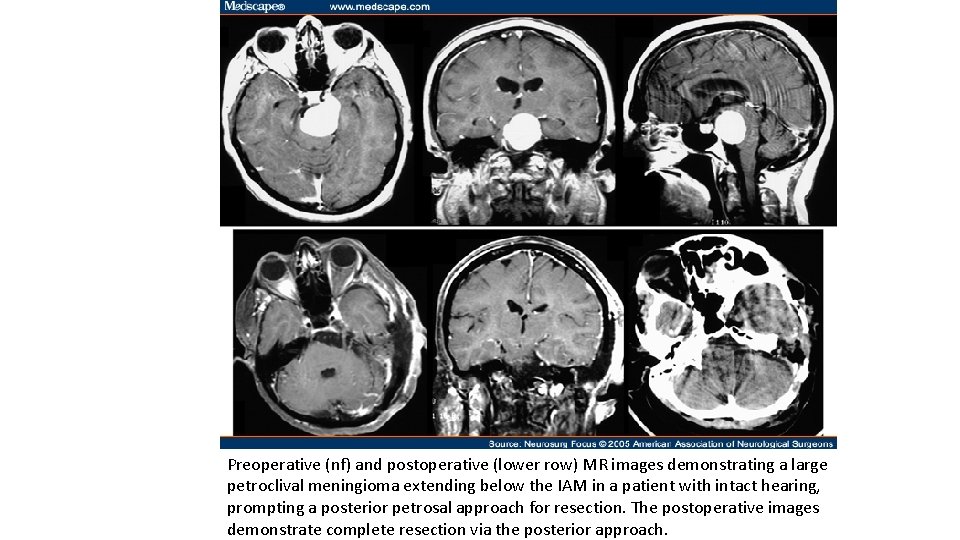

Preoperative (nf) and postoperative (lower row) MR images demonstrating a large petroclival meningioma extending below the IAM in a patient with intact hearing, prompting a posterior petrosal approach for resection. The postoperative images demonstrate complete resection via the posterior approach.